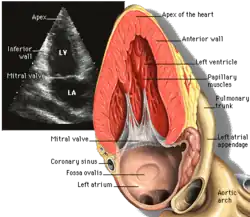

Parasternal long axis (PLAX)

This view is obtained to the left of the sternum and views the heart in its long axis. In this view, the mitral valve, aortic valve, right ventricular outflow tract, base of the left ventricle, and the left atrium can be visible. Angulation in this view can bring the right ventricular inflow tract and tricuspid valve into view, and angulation the opposite way can bring the pulmonary valve into view.

In this view, it is possible to appreciate the long-axis cross section of the mitral and aortic valves. The classic "hockey stick" shape of rheumatic mitral stenosis can be appreciated in this view. However, the angle of the probe with these valves can lead to under-appreciation of valve dysfunction.

The parasternal long view of the pulmonary valve is the only view of the posterior leaflet.

Structures visible:

- Anterior septal and inferior lateral walls of the left ventricle

- Left atrium

- Mitral valve in long-axis with chordae

- Aortic valve in long-axis

- Tricuspid valve in long-axis (angulated) and right ventricular inflow tract

- Pulmonary valve in long-axis (angulated) and right ventricular outflow tract